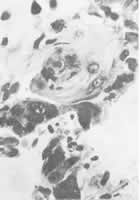

丙医师(病理科) 该病人尸解病理主要发现是:肝、骨(颈1~2和右髂)和食管均有鳞状细胞癌(见图1~3)。根据癌细胞的形态特点和发生部位,患者的原发癌灶可肯定在肝脏,而骨和食管则为转移癌,因为原发性骨癌不可能有鳞状细胞癌,食管发生的鳞状细胞癌,癌灶绝不会发生在浆膜层,而食管黏膜正常。

图1 原发性肝癌灶,左下角可见正常肝组织HE×100

图2 原发性肝鳞状细胞癌,中央部可见角化珠 HE×600

图3 脊椎骨转移的鳞状细胞癌 HE×200